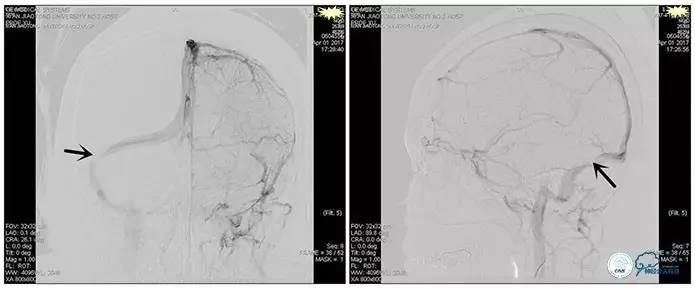

术中测压

远端压力:530mmH2O

近端压力:120mmH2O

术中造影

术后造影

狭窄较前有改善

术中测压:

远端:520mmH2O,

近端:190mmH2O。

治疗方案:

1、8mm×40mm , EverCross球囊扩张;

2、8mm×40mm,Protégé自膨支架成形术。

术后右侧ICA造影

术后远、近端压力差为:0

术后右侧ICA斜位